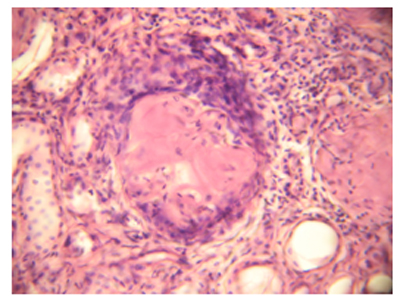

Ուսումնասիրված դեպքերից 52-ում հայտնաբերվել է փայծաղի տարբեր աստիճանի արտահայտված ամիլոիդոզ: 16 դեպքում (30,7%) սագոյի փայծաղի պատկեր է դիտվել` ավշային ֆոլիկուլներում ամի-լոիդի նուրբ դեպոզիտներով կամ ավելի ընդարձակ կուտակումներով, ընդհուպ ֆոլիկուլի ամբողջական զբաղեցումը ամիլոիդով (նկ. 3): 28 դեպքում (53,8%) դիտվել է ճարպային փայծաղի պատկեր` ամիլոիդի առատ կուտակումներով ինչպես ֆոլիկուլներում, այնպես էլ արտաֆոլիկուլային դիֆուզ ավշային հյուսվածքում, անոթների պատերում: Հայտնաբերվել է փայծաղի պատիճի լավ արտահայտված սկլերոզ և հիալինոզ, իսկ որոշ դեպքերում այն ուղեկցվել է ամիլոիդային զանգվածների կուտակումներով պատիճում (նկ. 4), իսկ 8 դեպքում (15,4%) փոփոխությունները փայծաղում միջանկյալ բնույթ են կրել:

Վիրահատական բիոպսիոն և աուտոպսիոն նյութի ուսումնասիրությամբ վահանագեղձում հայտնաբերվել է հենքի զգալի ամիլոիդոզ` ուղեկցված ֆոլիկուլների ապաճումով: Դրանց հարակից հայտնաբերվել են կիստոզ լայնացած ֆոլիկուլներ (նկ. 5): Ամիլոիդոզն արտահայտված է եղել հատկապես մանր անոթների պատերում: Որոշ տեղամասերում ամիլոիդային կուտակումներին կից հայտնաբերվել են արտահայտված լիմֆոցիտար, պլազմատիկ բջջային ներսփռանքներ` ուղեկցված հսկաբջջային ռեակցիայով: